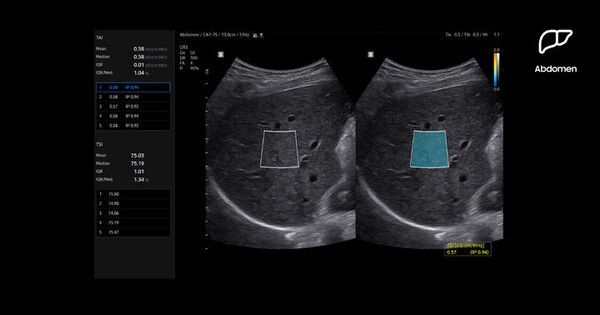

삼성메디슨이 지난 9월 대한영상의학회 (KCR 2025)를 통해 국내 공개한 영상의학과 프리미엄 초음파 진단기기 R20은 일관된 진단 품질을 유지할 수 있도록 의료진을 지원해 관련 역량을 개선했다. R20의 핵심 기능인 라이브 리버 어시스트(Live LiverAssist)는 딥러닝 기반 인공지능(AI) 진단 보조 기술이다.

특히, R20은 간 지방 정량 측정 AI 기반 기능을 통해 정밀한 진단을 가능하게 한다. 티에이아이 (TAI·Tissue Attenuation Imaging)는 초음파 신호를 간세포 내 지방에 의해 약해지는 정도를 측정해 실시간으로 지방간 변화를 평가한다. 티에스아이 (TSI·Tissue Scatter distribution Imaging)는 조직 산란 분포를 정량적으로 측정해 지방간 진행 상황을 모니터링한다.

에스-쉬어웨이브 이미징 (S-Shearwave Imaging)은 비침습적으로 유방, 간, 근골격계 등 다양한 부위의 조직 및 병변 탄성도를 평가할 수 있다. 부위에 따라 색으로 구분된 영상 화면과 정량화된 수치, 관심 영역(ROI)을 지정할 수 있는 기능을 통해 의료진이 유방 및 간질환을 더욱 정확하게 진단할 수 있도록 지원한다.